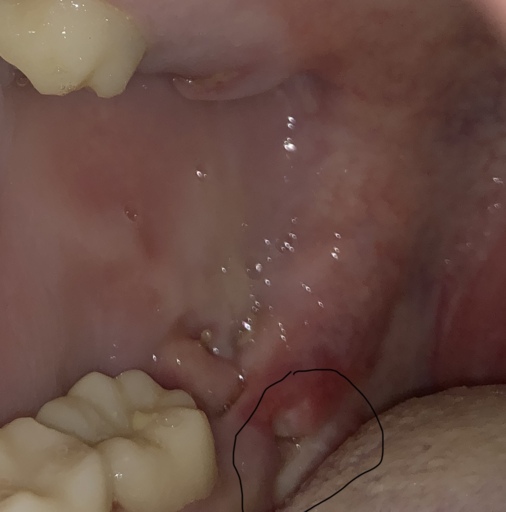

Hi, I have a frenulum on the right side of my mouth. It connects to my gums about 1cm behind the upper and lower back molars. It has become tight and painful. Have you ever seen anything like this? Is it safe to have it cut? I will attempt to add a photo. Thank you, H. Jay Graber

A frenum or frenulum is a small fold of tissue that restricts and secures the motion of a mobile organ.  I have not heard of a frenulum in the back of the mouth. It would be best to bring this to the attention of your dentist, especially because it is causing discomfort.  I did not see a picture attached to your question, however I am wondering if it is part of your cheek or possibly an impacted tooth that may be causing this discomfort.  Use warm salt water rinses several times a day to soothe the tissues until you have a proper exam and diagnosis.

A frenulum or frenum is a small fold of tissue that restricts or secures the motion of a mobile organ.  I have not seen a fold of tissue (unless sutured) that connects distal to the molars.  There is a frenum that connects your tongue to the floor of your mouth as well as one that attaches your lips to your jaws.  Since you are experiencing pain, it is important for you to see your dentist immediately to be sure you do not have an infection or a tooth that is creating swelling in the area.